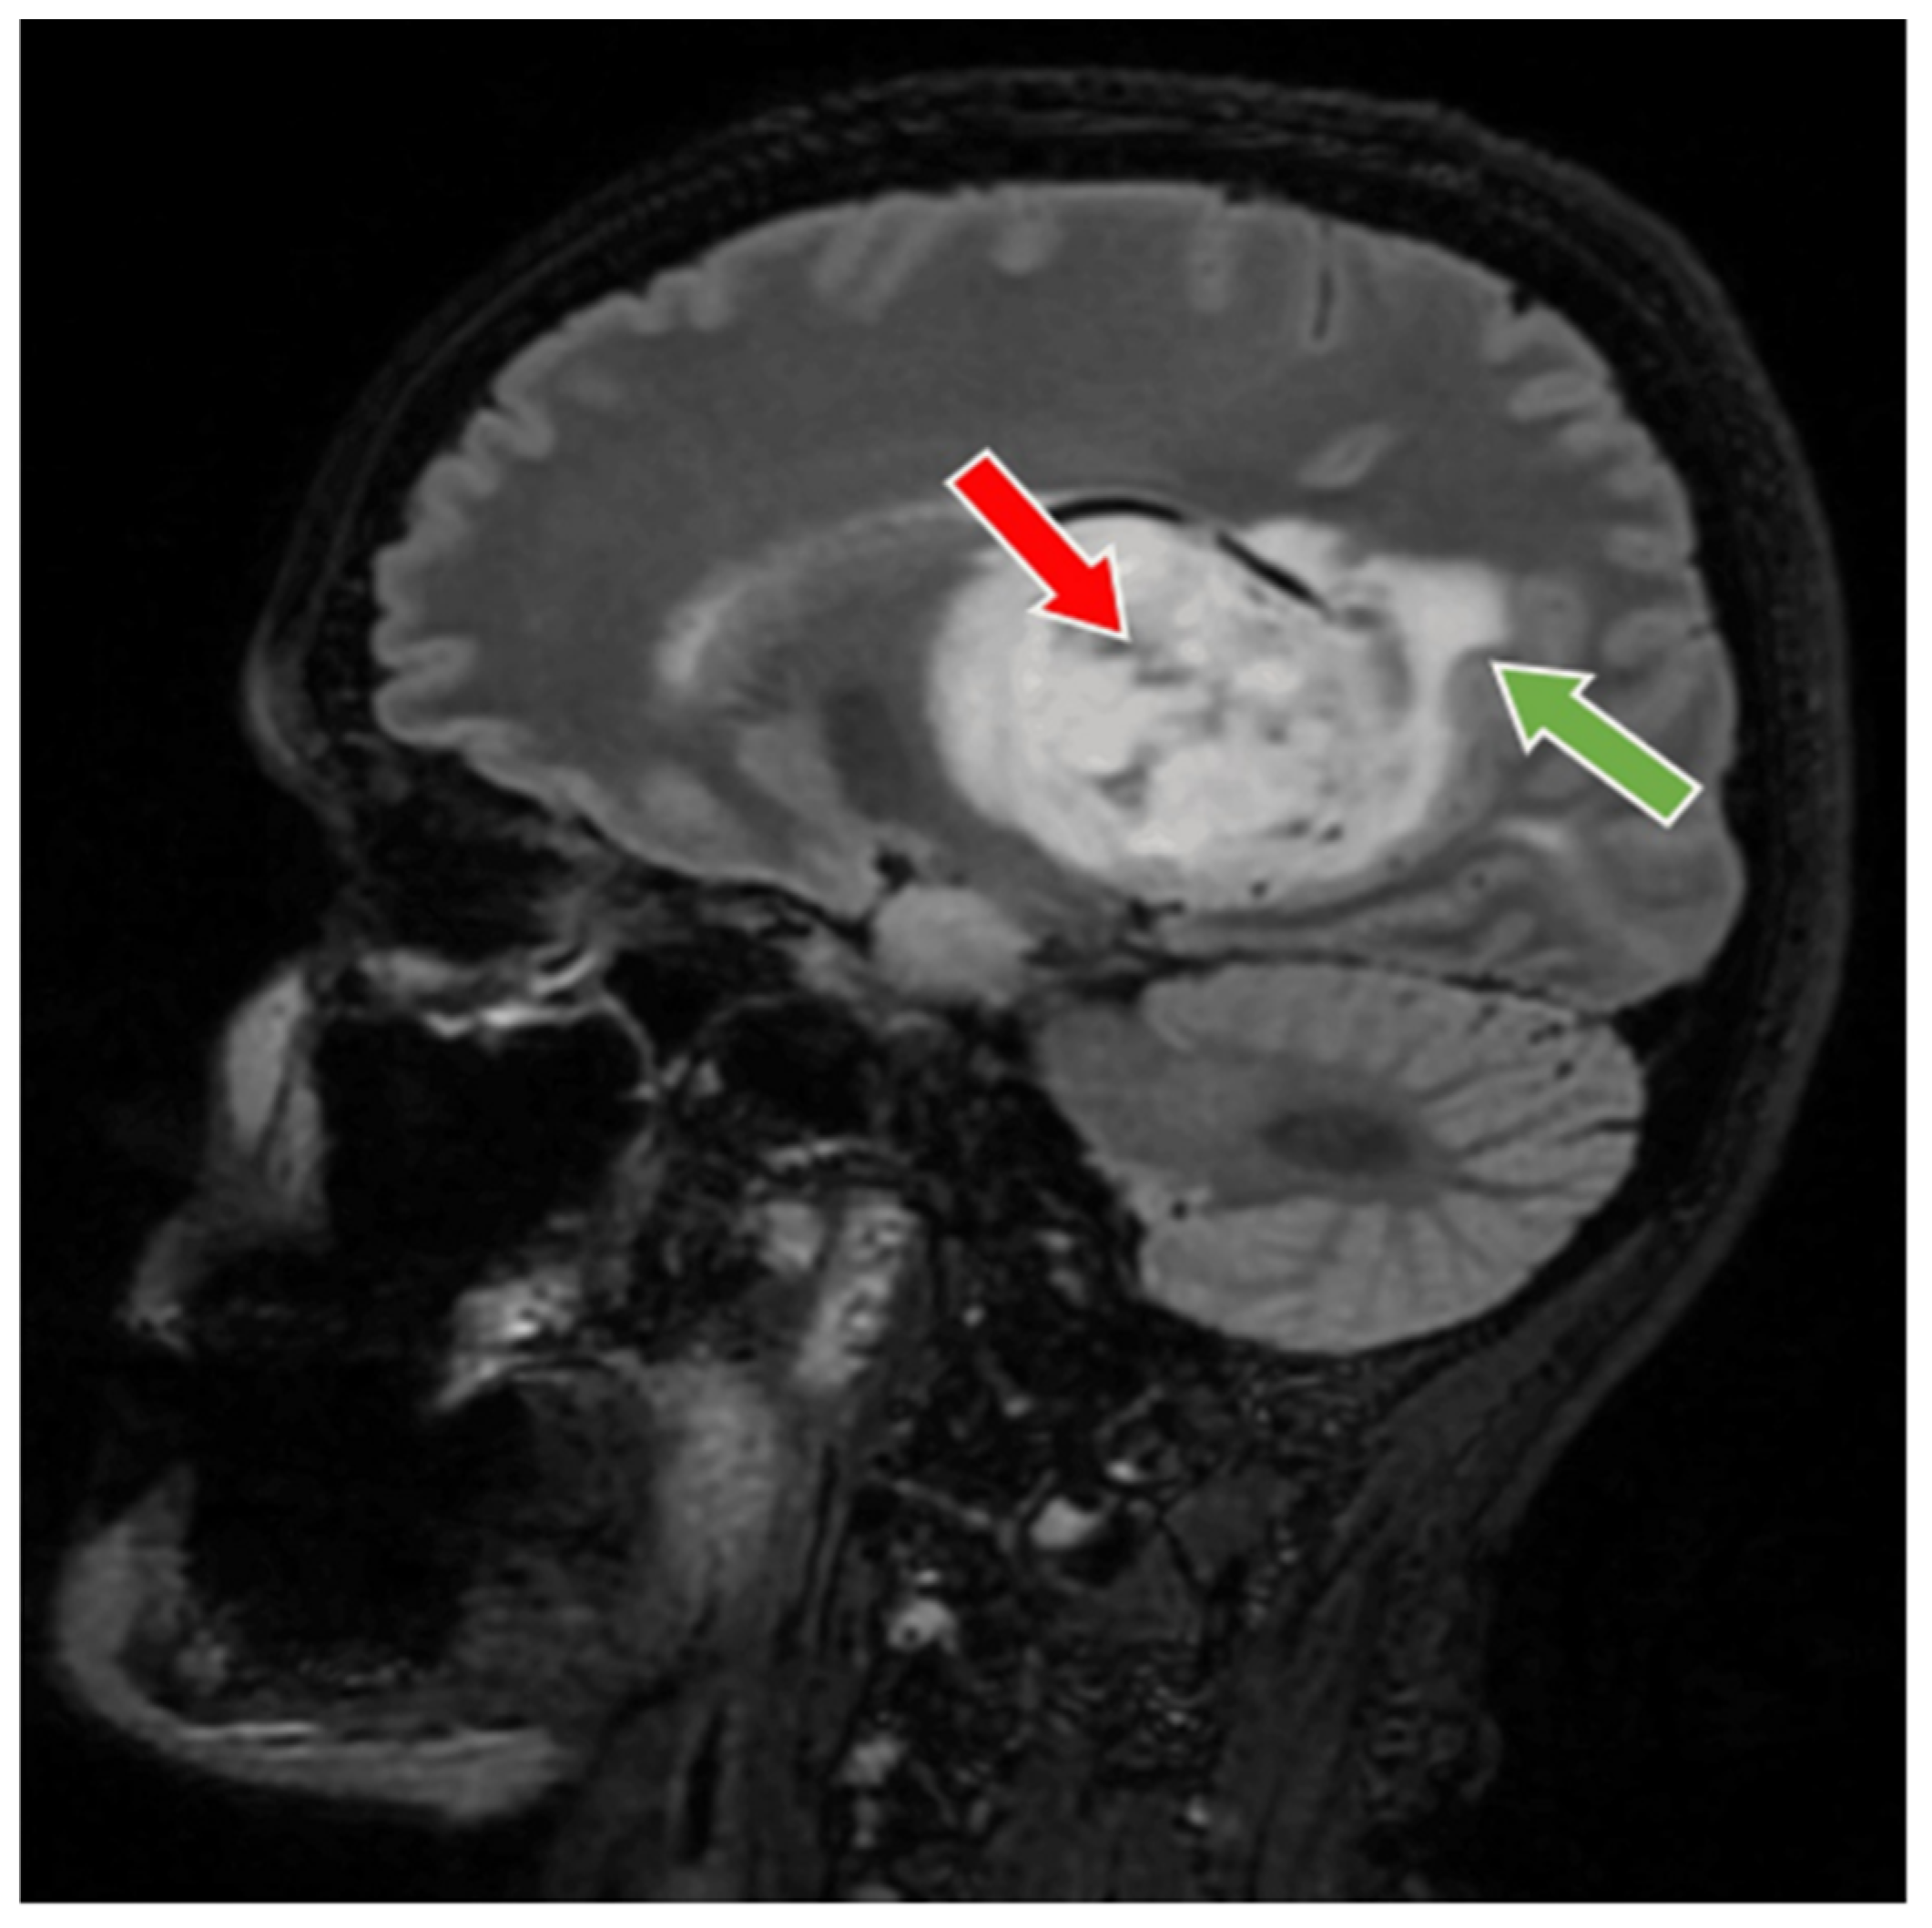

Figure 3. Preoperative MRI T2-FLAIR sequence, sagital section. MRI T2-FLAIR sequence sagital section depict a thalamic glioma (red arrow), with an infiltrative character suggestive of a high-grade glioma (green arrow). The glioma has a diameter of 6 cm.

56-year-old female patient presented in our clinic with persistent cephalalgia, nausea, vomiting, and gait disorders (gait apraxia) occurring for approximately 2 months with progressive intensification of symptoms. Neurological examination revealed a syndrome of intracranial hypertension, right central type facial paresis, and right hemiparesis predominantly brachial. On objective examination, the patient showed clinically normal lungs and cardiovascular assessment showed an arterial hypertension grade II and hypertensive retinal angiopathy stage II. A cranial computed tomography (CT) scan was conducted, which disclosed the presence of a neoplasm located in the right thalamus, measuring 5.5 by 6 cm. This lesion exhibited a hypodensity relative to the surrounding cerebral tissue in the pre-contrast phase and demonstrated moderate inhomogeneous enhancement following the administration of an iodinated contrast agent. There was a significant mass effect on the third ventricle, accompanied by a notable midline shift of approximately 1 cm, indicative of subfalcine herniation. Apart from the described pathology, the cerebroventricular system presented a normal tomodensitometric appearance. Native brain MRI with paramagnetic substance highlighted the previously described tumor formation, hypointense in T1 and hyperintense in T2 with discrete and inhomogeneous intake after administration of gadolinium DTPA and infiltrative character suggestive of a high-grade glioma. Otherwise, the normal appearance of the brain was highlighted in the T1 and T2 weighted sequences and after administration of paramagnetic substance (Figure 1, Figure 2 and Figure 3). The cystic component of the lesion was characterized by a cyst containing fluid of a yellowish hue and oily consistency, exhibiting a density exceeding that of cerebrospinal fluid, indicative of its hematogenous origin (absorbed blood). The solid portion is highly vascularized, presenting a reddish coloration and possessing a soft texture amenable to aspiration.